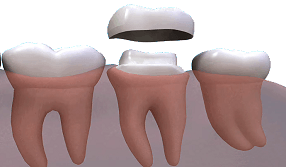

Cfare jane kellefet dentar?

Kellefet jane kurora artificiale ne formen e dhembit.Ato vendosen mbi dhembin e preparuar (ose kultin ),per ta mbrojtur ate dhe per te permiresuar anen estetike .

Kur jane te nevojshme kellefet dentar?

Per te mbrojtur nje dhemb te dobet (psh qe ka qene shume i prishur )dhe ka mbushje masive

Riparimin e nje dhembi te thyer

Si pjese perberese e urave

Per mbulimin e implantit

Per mbulimi e nje dhembi qe ka ndryshuar ngjyre ose ka forme jo estetike

Per te bere modifikime estetike